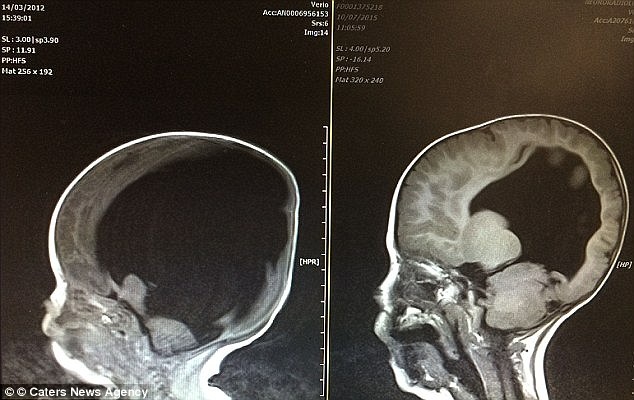

| Hình ảnh quét não bên trái cho thấy hộp sọ của Noah khi mới sinh chứa đầy chất lỏng màu đen và rất ít mô não khỏe mạnh. Bên phải là bộ não hiện tại của cậu bé, gần như phát triển đầy đủ. Ảnh: Dailymail. |

Ngay từ khi sinh ra vào năm 2012, cậu bé Noah chỉ có 2% bộ não, nằm thành một lớp mỏng ít ỏi, chủ yếu tập trung ở phần trước hộp sọ. Cậu bé còn bị chứng dị tật nứt đốt sống gây thoát vị màng tủy. Các bác sĩ cho biết chỉ 1 trong 2 vấn đề đã đủ để đứa trẻ không thể sống sót và cho dù sống được cũng tàn phế nặng nề.

Tuy nhiên, thật kỳ diệu, Noah vẫn tiếp tục phát triển và bộ não của cậu, đến năm 3 tuổi, đã phát triển được 80% so với người bình thường.